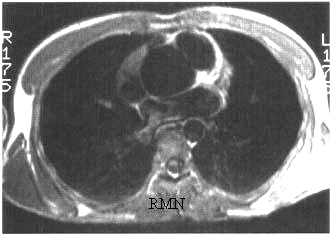

TC e RM

Sono metodiche sicuramente appropriate nella diagnostica degli aneurismi toracici e toracoaddominali.

La RM, oltre alla valutazione dimensionale e morfologica dell'aorta toraco-addominale, con la sequenza cine-RM e phase-contrast è in grado di valutare eventuali stenosi o insufficienza della valvola aortica e differenziare la componente trombotica endoluminale dal flusso ematico senza infusione di mezzo di contrasto. L'intensità di segnale del trombo, nelle sequenze Spin Echo T1 e T2 , consente di evidenziare componenti trombotiche emorragiche o di deposizione recente, ( che presentano segnale iperintenso).

L'ANGIO-RM, con somministrazione di mezzo di contrasto endovena, consente di ottenere immagini angiografiche multiplanari e tridimensionali, dell'intera aorta e delle arterie iliache, in tempi di scansioni molto brevi (da 20 secondi a 3 minuti) con una buona valutazione di eventuali lesioni associate interessanti i vasi epiaortici o viscerali.

Una limitazione relativa allo studio RM è rappresentata dal paziente acuto, emodinamicamente instabile, per cui valgono le stesse considerazioni della dissezione (scarso controllo del paziente durante l'esame e necessità di apparecchiature dedicate alla valutazione della pressione arteriosa e della saturazione di ossigeno).